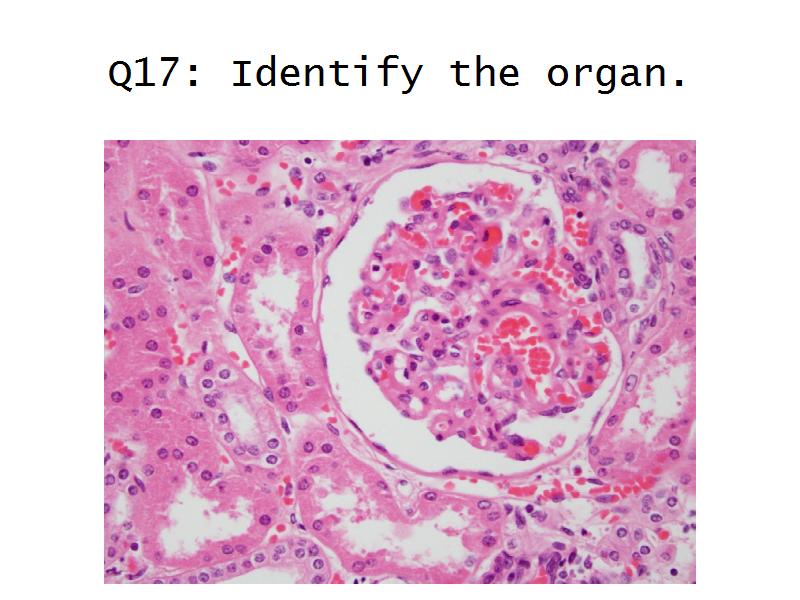

Kidney

Slides 28 & 76

Kidney: Objectives

- Basic anatomy of the kidney

- Basic arrangement of nephrons and collecting tubules in the kidney

- Structure of the nephron and collecting tubules

- The renal corpuscle

Kidney: Tasks

- Make an annotated drawing of the macroscopic view of the kidney.

- Make an annotated diagram of a nephron, including the juxtaglomerular apparatus. Indicate the flow of blood and water in each part, and how solutes are filtered, secreted and reabsorbed.

- Complete the drawings for each slide in the practical workbook.